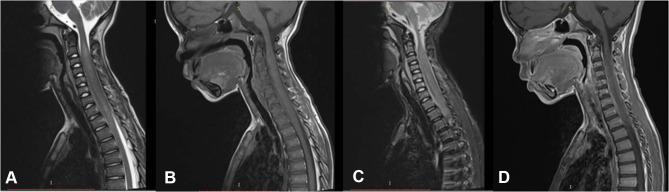

An 8-year-old male presented with a one month history of nuchal pain followed by stiffness and rapidly progressive upper and lower limb weakness. He was seronegative for HIV and EBV. Computed tomography myelogram and magnetic resonance imaging of the cervical and thoracic spine showed a long segment (C2 to T1) complete absence of cerebrospinal fluid signal and mildly enhancing intradural extramedullary lesion with an extradural and right paravertebral muscle extension, respectively. Post-excision biopsy histopathology and immunohistochemistry confirmed the diagnosis of a CD 10+, CD20+, CD45+, Bcl-2+, Ki67+, and EBER in situ hybridization for EBV negative, Burkitt's lymphoma (BL). Cytogenetic analysis showed chromosomal translocations of 8q24. CHOP plus intrathecal cytarabine, methotrexate was given as chemotherapy regimen. 1.8 grays (Gy) per fraction to the local area for an average total dose of 36 Gy was given with a resultant significant clinical improvement.

一名8岁男性,有1个月颈部疼痛病史,随后出现僵硬以及快速进展的上下肢无力。他的HIV和EBV血清学检测均为阴性。颈椎和胸椎的计算机断层扫描脊髓造影和磁共振成像显示长节段(C2至T1)完全没有脑脊液信号,硬膜内髓外病变轻度强化,分别伴有硬膜外和右侧椎旁肌肉延伸。切除术后活检组织病理学和免疫组化确诊为CD10 +、CD20 +、CD45 +、Bcl-2 +、Ki67 +,EBV原位杂交阴性的伯基特淋巴瘤(BL)。细胞遗传学分析显示8q24染色体易位。化疗方案为CHOP加鞘内注射阿糖胞苷、甲氨蝶呤。对局部区域给予每次1.8戈瑞(Gy),平均总剂量为36 Gy,临床症状得到显著改善。